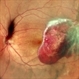

- Proliferative Diabetic retinopathy, Diabetes

- Proliferative Diabetic Retinopathy